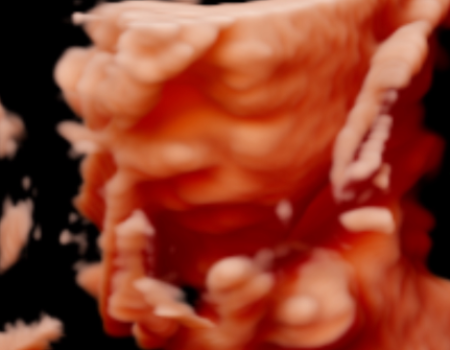

¡La ecografía 5D es una imagen en tres dimensiones y en tiempo real, como la 4D, pero en la que el tratamiento de las imágenes en el ordenador permite suavizar las texturas, modificar el color de la imagen y aplicar un foco de luz desde diferentes ángulos de forma que se crean luces y sombras y esto le da una imagen más real.

La Ecografía 5D incorpora un procesamiento más avanzado que optimiza la iluminación, la textura y la profundidad de la imagen, logrando una representación más clara y uniforme del bebé. Gracias a estos ajustes, los rasgos faciales y los movimientos se aprecian con mayor naturalidad, reduciendo imperfecciones visuales propias de otras modalidades y ofreciendo una imagen final más definida y comprensible para las familias.